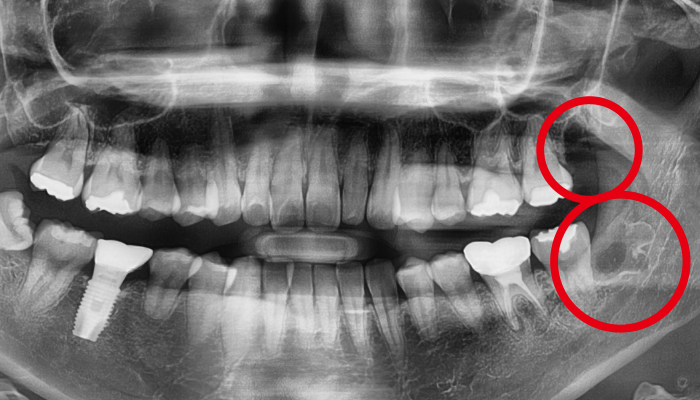

사랑니 발치 전후 사례

• 치료 전

치료 후

• 치료전

치료후